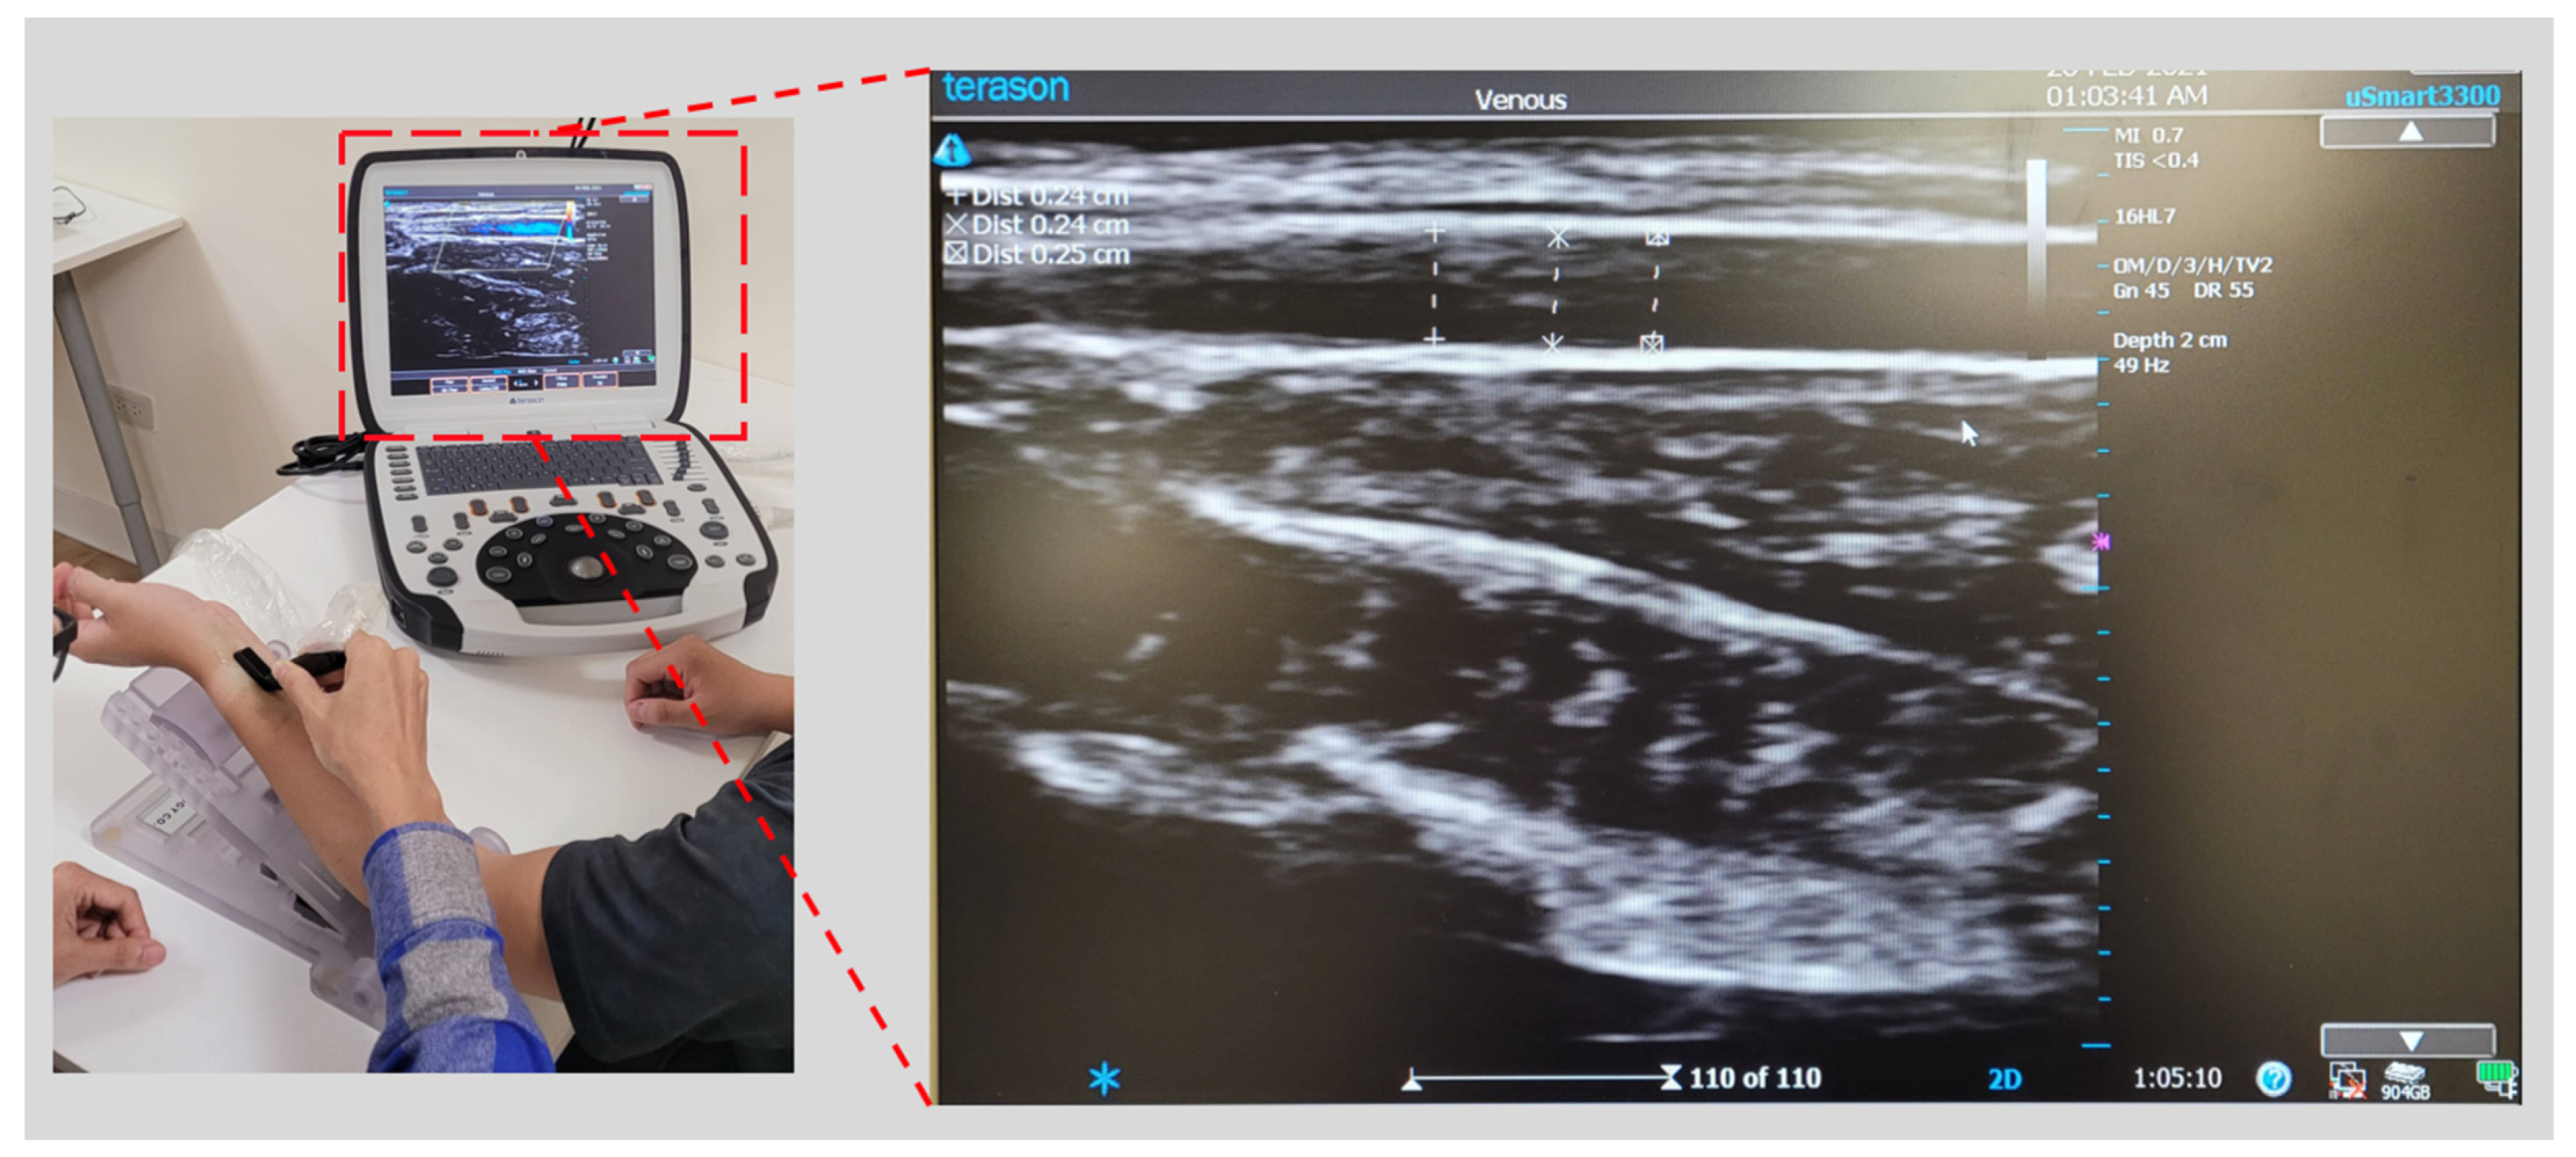

To improve the accuracy of the BP estimation model in this study, it was necessary to measure the patient’s arterial compliance. We used the PPG sensor to quantify the patient’s arterial dimensions and arterial change. The PPG sensor we used is a diffuse reflectance spectroscopy (DRS) sensor that integrates three wavelengths of light-emitting diode (LED) and a photodiode (PD) [36] to ensure that the PPG sensor is placed on the skin surface parallel to the radial artery. When the piezoelectric sensor array of the cuffless BP monitor detects the pulse wave, it will determine that the SNR of the pulse wave qualified the set threshold, indicating that the device is placed on the artery. At this point, the PPG sensor is activated to sense the optical signal of arterial change. When the photons excited by the PPG sensor enter from the epidermal tissue and return to the PD, the optical information of the tissue can be obtained [37]. The depth of the photons entering the tissue depends on the distance of LED to PD and wavelength. To measure the optical characteristics of the tissue as deeply as possible, we chose infrared light with a wavelength of 880 nm as the PPG signal for our estimation of arterial changes. The ADC sampling rate is 100 Hz and the resolution is 18 bits, because infrared light can enter the tissue more than visible light. The deeper the depth, the more tissue optical information can be obtained [38,39]. The distance between the LED and PD is 3 mm. Since the light path of the photon in human tissue is banana-shaped [40], the detection depth can be greater than 3 mm, which affects the radial artery depth. The main factor is the body mass index (BMI) [41]. In most cases, the radial artery depth is approximately 2.5 mm in individuals with a BMI of less than 30 [42,43]. After determining that the PPG sensor has known physical parameters and the radial artery’s physiological characteristics, we used an ultrasonic imaging device as a reference instrument to model the arterial parameters measured by ultrasonic imaging and the quantized PPG signal [44]. The instruments we used included an ultrasonic imaging device (a uSmart 3300, produced by Terason, Burlington, MA, USA) and an L-type probe (a 16HL7, produced by Terason Inc., Burlington, MA, USA) to sample the radial artery parameters of the participants. The researcher operated the L-type ultrasound probe to collect an ultrasound image of the participant’s radial artery and measured the depth, diameter, change, wall thickness, and other information (see Figure 7).

Figure 7.

Ultrasound image acquisition of radial artery.